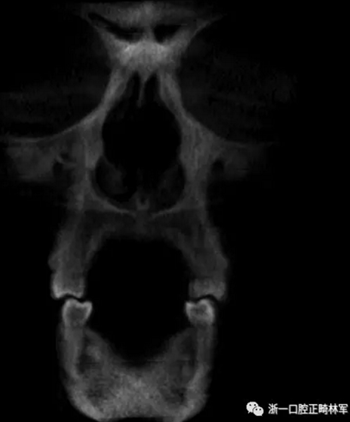

然而,CBCT成像也具有較大的限制:有限的分辨率,牙體組織的不準確表現(xiàn),以及當患者在咬合位或者完全牙尖交錯位CBCT掃描時,上頜骨和下頜骨牙齒之間發(fā)生的混合(圖1)。 這種混合使上頜骨與下頜骨牙齒的自動分離復雜化,并且由于咬合解剖結構和細節(jié)的不準確而使人工分離變得困難。

圖1. 在CBCT中咬合時上頜牙齒和下頜牙齒咬合面的混合和咬合細節(jié)的喪失。